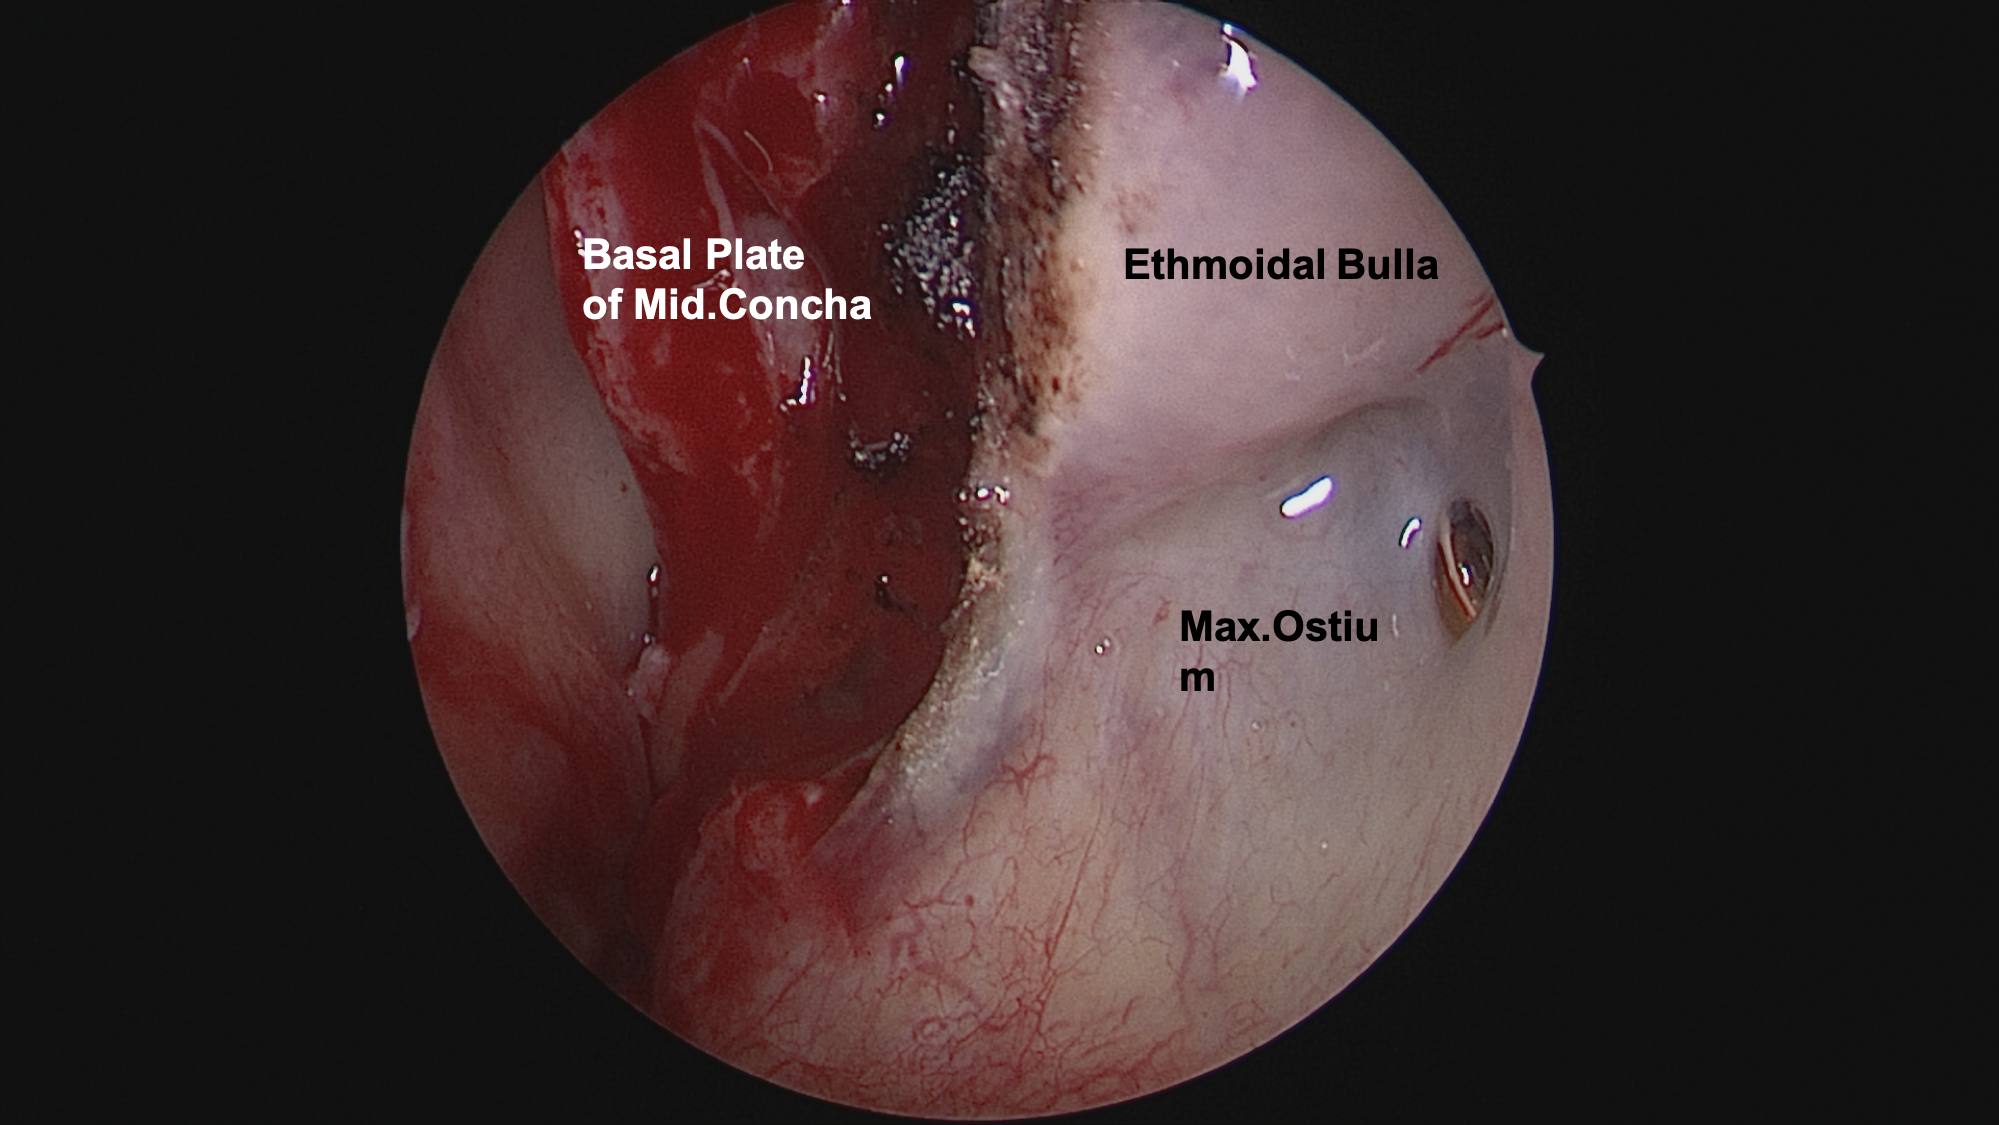

图5.收敛双侧鼻腔后,暴露并切除左侧中鼻甲、钩突

图6.术中电凝出血的蝶腭动脉(SPA)

图7.咬除上颌窦后壁及腭骨垂直板

图8.见腭骨垂直板被肿瘤侵犯变薄,打开上颌窦内侧壁进入上颌窦,见上颌窦后壁被肿瘤挤压后菲薄,给予咬除上颌窦后壁以及残留的腭骨垂直板。